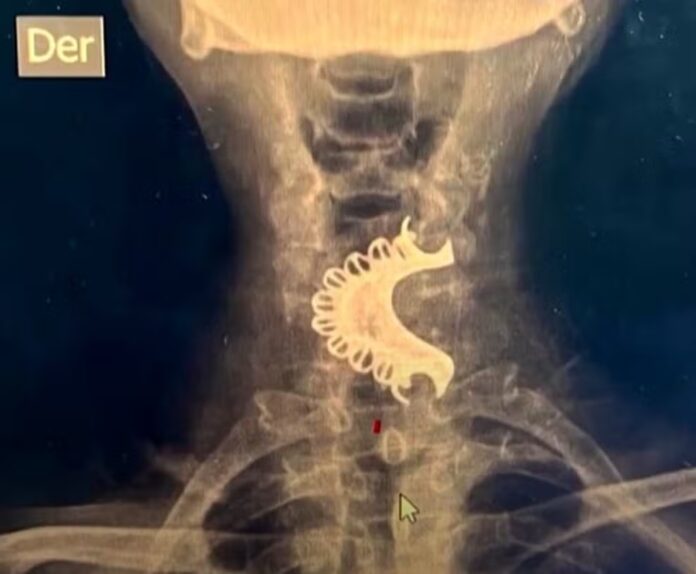

Quatro dias após o incidente, o homem começou a apresentar dificuldade para respirar e decidiu procurar atendimento médico. Durante um exame de raio-x, os médicos identificaram que a dentadura estava alojada em sua garganta, sendo necessária a intervenção cirúrgica para sua remoção.